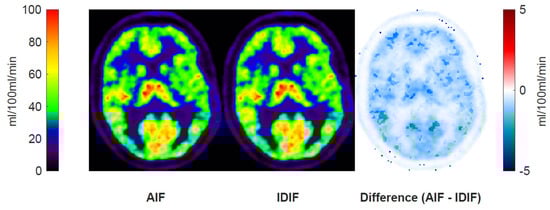

A regional perfusion parameter maps, K1, using the AIF and IDIF are shown in Figure 4, along with a subtraction map. The difference map shows a small absolute difference between the rest and acetazolamide conditions of below 2 mL/100 mL/min.

Figure 4.

Perfusion (K1) maps and the absolute difference of these from a representative subject subjected to delay- and dispersion-corrected IDIF and AIF. Generally, very small differences in perfusion were observed.